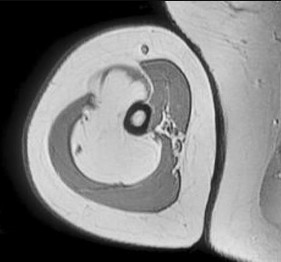

Figures 6a through 6d are the radiographs and T1-weighted sagittal and fat-saturated axial MR images of an otherwise healthy 56-year-old man who has anterior knee pain and intermittent swelling after sustaining a noncontact twisting injury. Low-power and high-power hematoxylin and eosin stained histologic specimens are shown in Figures 6e and 6f. Based on the history, radiographs, CT scan, MR imaging, and histologic findings, what is the most likely diagnosis?

The lesion in the posterior intercondylar knee notch is a benign synovial hemangioma. Intralesional calcifications, classically associated with hemangiomas, are frequently not identified on plain radiographs. The MR imaging reveals a hypervascular lesion with multiple filling defects, with hyperintensity on T2-weighted images and low-to-intermediate signal intensity on T1-weighted images. Histologically, vascular lakes within fine capillaries with a synovium on the surface of the lesion are characteristic of this condition. Many patients with synovial hemangioma have pain, swelling, stiffness, or mechanical symptoms. The correlation of symptoms with the hemangioma for this patient is unclear because there was recent trauma and a concurrent meniscus tear. Simultaneous treatment of both potential sources of pain is typically recommended. As with PVNS, the disease can be localized or diffuse. Surgical excision, either open or arthroscopic, is the recommended treatment. PVNS is the most common intra-articular tumor, but hypointensity in either the diffuse or localized type is characteristic in both T1- and T2-weighted images. Synovial sarcoma, although often found close to a joint, is not characteristically found within a joint.